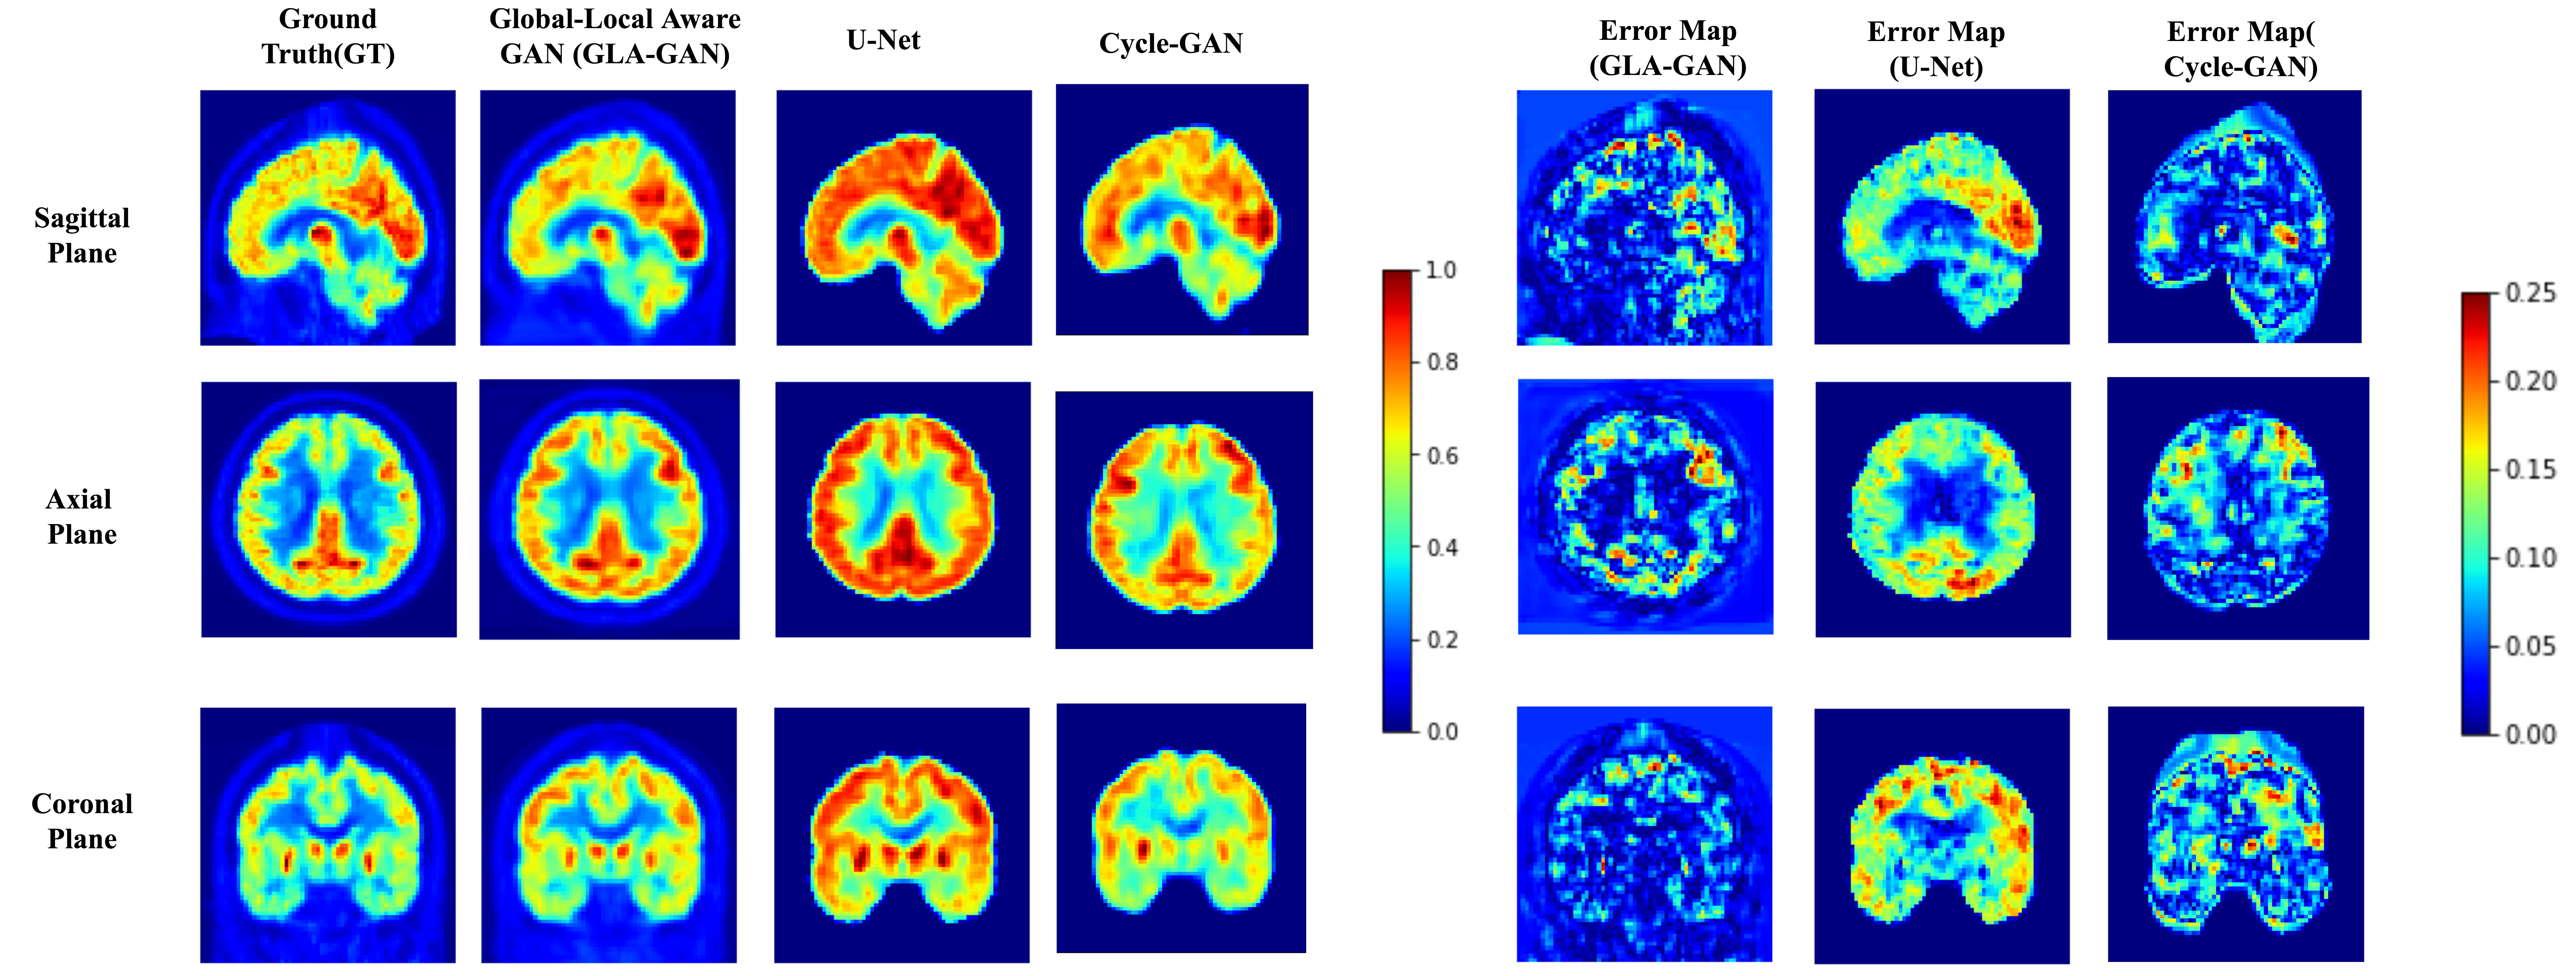

Refer to caption

Figure 5: (a)

Figure 6: (b)

Figure 7: Qualitative comparison of PET scans synthesized using GLA-GAN, 3D-U-NET and Cycle-GAN. Ground truth and estimated PET scan along with error maps corresponding to each of the models is presented for an AD (a) and CN (b) sample in axial, coronal and sagittal views. [Best viewed in color]

Firstly, we demonstrate the significance of incorporating both global and local contextual information simultaneously through parallel modules in the GLA-GAN framework. To this end, we compare three variants of the multi-path architecture: (i) Global GAN, (ii) Local GAN and (iii) Global-Local GAN. Figures 4 (a) and (b) show qualitative visualizations of PET scans synthesized using these three models along three planes (axial, sagittal and coronal) for an AD and CN sample respectively. In addition to the generated images, error maps with respect to the ground truth are also presented. Although not readily apparent, there are subtle differences in the estimates generated by the individual Global and Local only modules. A closer observation reveals that while the local module is better at capturing intricate details like the shape of ventricles, the global module achieves better estimate of the FDG uptake intensity. However, it is clearly evident from both synthesized images and error maps that the hybrid model predicts the FDG uptake patterns for both classes of samples (AD and CN) most accurately.

Next, we benchmarked our proposed GLA-GAN model against three state-of-the-art models: (i) 3D U-NET based autoencoder [24], (ii) Standard GAN with L1 & SSIM Loss terms and (iii) Cycle-GAN [25]. Figure 7 shows qualitative comparison of GLA-GAN with these three models. As Cycle-GAN is based on a global transformation framework, it is able to discern general variations in uptake patterns of AD and CN classes. However, it fails to capture local contextual details as evident from the discrepancy in the shape and uptake in ventricles depicted in both the axial and coronal planes when compared to the ground truth PET scan. On the other hand, the 3D U-NET produced very generic and blurry estimates of the real PET scans. In comparison to these global methods, the results clearly indicate the superiority of our GLA-GAN model in accurately synthesizing PET scans without loss of details. Additionally, quantitative evaluation of these models based on three quality assessment metrics is provided in Table 1. The GLA-GAN framework provides either on-par (statistically insignificant difference) or better performance than competing methods across these metrics. While it provides the lowest MAE, there was no significant difference for PSNR and SSIM (p=0.1690𝑝0.1690p=0.1690 and p=0.1363𝑝0.1363p=0.1363 using paired, two-tailed, T-test) when compared to the best performing model.